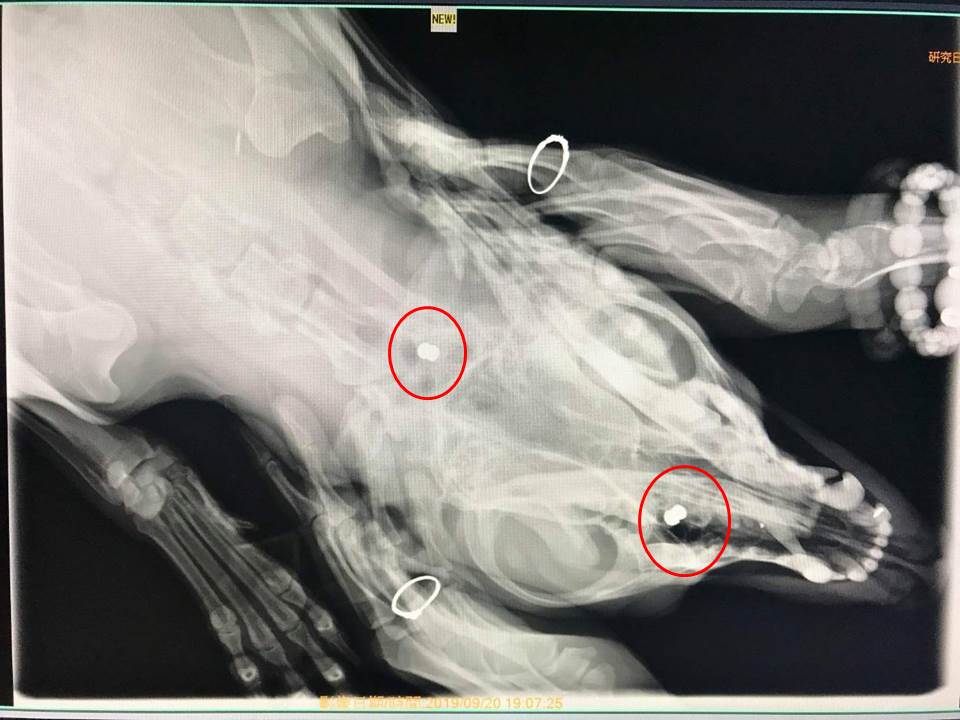

愛犬遭不明人士傷害的巫姓飼主表示,9月17日晚上10點30分左右,飼養在自家工廠前私有空地的2隻狗突然哀嚎的很大聲,於是前往查看發現其中一隻名為「將軍」黃狗倒在地方不斷哀號,且口鼻血流不止,另一隻黑狗則是不停吠叫。隨後將「將軍」緊急送醫檢查,醫生一共在狗狗身上發現3處彈痕,分別在肩胛骨及頸部各有0.5公厘的傷口,經過X光片檢查肩胛骨、頸部及鼻腔內都留有疑似鉛彈的彈頭,所幸這幾顆鉛彈沒有傷及要害,醫生順利將彈頭取出後,「將軍」目前已無大礙,但仍在醫院照護中。